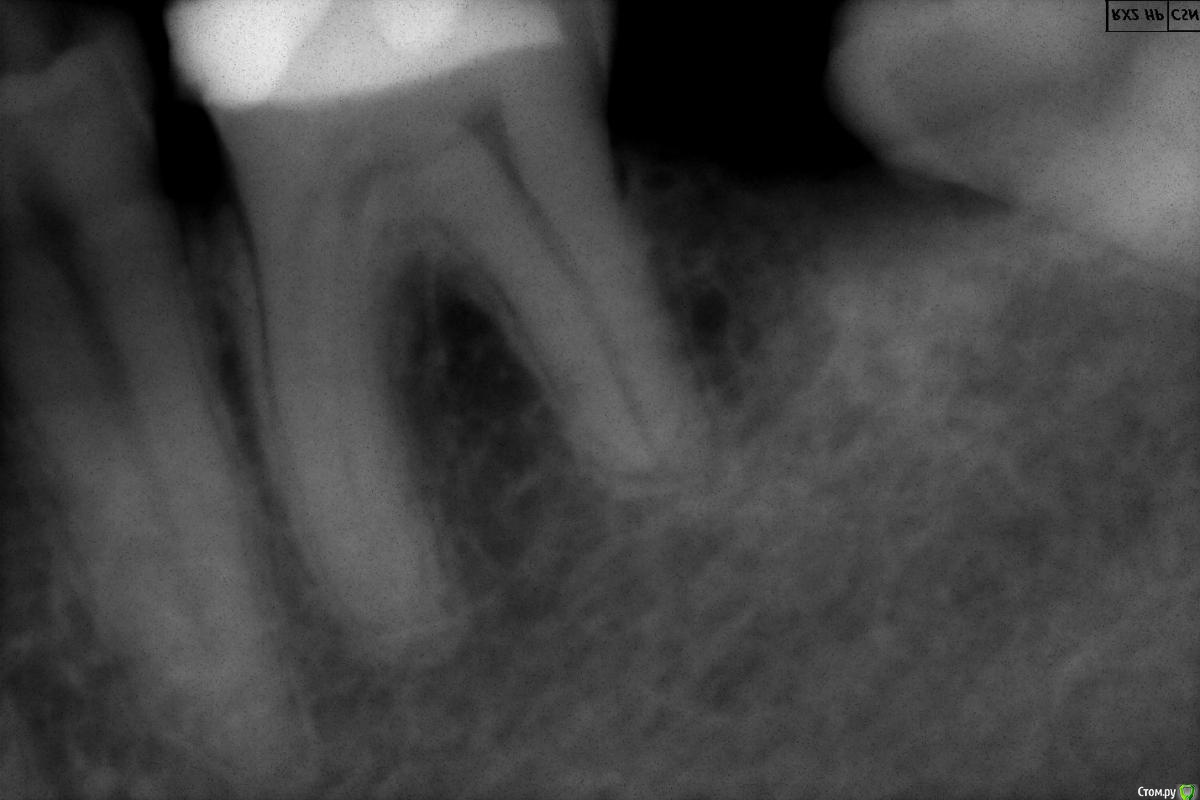

~~SERG~~ Опубликовано 26 декабря, 2016 Автор Поделиться Опубликовано 26 декабря, 2016 (изменено) А вот состояние 46 зуба на сегодняшний день. пошла резорбция корня со стороны 47, да и сам 47 просится на перелечивание, там в другой клинике тоже умудрились два инструмента сломать! И тоже мне ничего не сказали! PS если ктото решит что 46й зуб потреля большой кусок корня то "в защиту" прилагаю снимок 36го зуба - корень со стороны 37го короче чем со стороны 35. Изменено 26 декабря, 2016 пользователем ~~SERG~~ Ссылка на комментарий

~~SERG~~ Опубликовано 10 мая, 2017 Автор Поделиться Опубликовано 10 мая, 2017 поднимаю тему - каналы 46 перелечены гуттаперчей. стоит вопрос о протезировании вкладкой и коронкой. что выбрать в качестве материала? можно выбирать между кобальтхромом и цирконием. Ссылка на комментарий